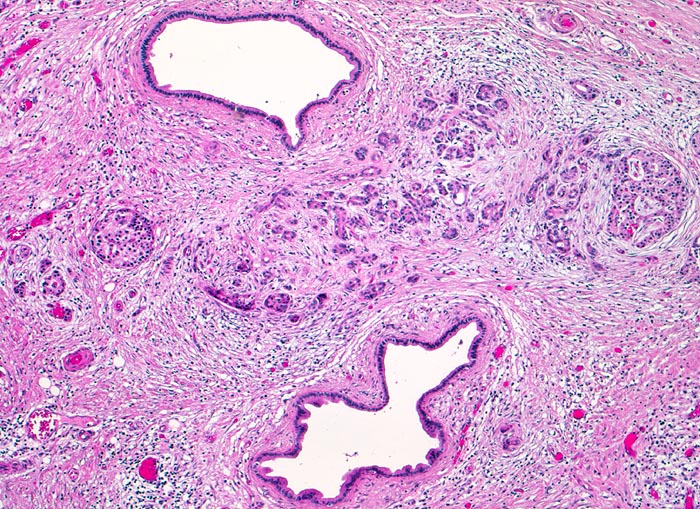

PathoPic – image database / PathoPic ID 4243 - chronische sekundäre obstruktive Pankreatitis

chronische sekundäre obstruktive Pankreatitis

Zwischen zwei dilatierten Pankreasgängen ist ein stark fibrosiertes Pankreasläppchen mit atrophen Acini erkennbar. Daneben ist eine erhaltene Insel erkennbar. Das Parenchym ist stark fibrosiert. Die andeutungsweise erkennbare Läppchenarchitektur und die fehlenden Zellatypien helfen zur Abgrenzung des entzündlich veränderten atrophen Parenchyms von einem Tumorinfiltrat (ungeordnete Drüsenschläuche).

Ursache einer obstruktiven Pankreatitis ist meist eine ausgeprägte Stenose des Hauptgangs, am häufigsten durch einen Tumor im Pankreaskopf. Weniger häufig sind große, nahe der Papille eingeklemmte Gallensteine. Durch den langzeitigen Gangverschluß kommt es zum Untergang aller stromaufwärts der Obstruktion liegenden Azinuszellen. Da es im Bereich der chronischen Pankreatitis und des Tumors (Desmoplasie) zu einer Fibrose kommt, ist es makroskopisch oft nicht möglich den Tumor von reaktiven Veränderungen abzugrenzen.